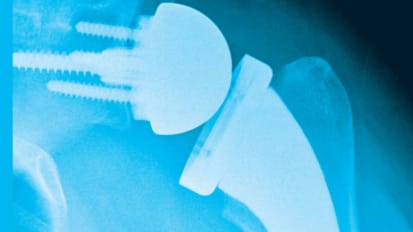

Study Aims to Improve Diagnosis of Infections Following Shoulder Surgery News

Study Aims to Improve Diagnosis of Infections Following Shoulder Surgery

The most common bacterial infection to occur after revision shoulder arthroplasty surgery can be diagnosed more accurately by considering how quickly samples of the microbe grow in hospital labs and the level of bacteria that grows, a study partly performed at UT Southwestern shows.